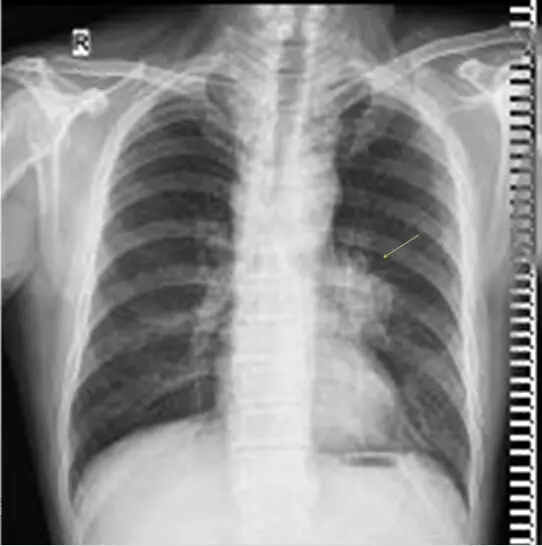

胸部:气管分叉管壁增厚,右肺上叶前段软组织结节形成,考虑肿瘤性病变可能大。

启示:医生在给病人查体的同时,要对患者胸部进行全面的检查,若不及时的发现,肺癌就很有可能会找上门。

影像诊断是非常重要的,因此我院专家组今日对肺癌影像诊断进行了讨论。专家组介绍到,在对胸部检查的同时,要着重检查胸部的正位和侧位,有些医院习惯性的只看正位而忽略了侧位,导致有些患者没有得到更准确的治疗。